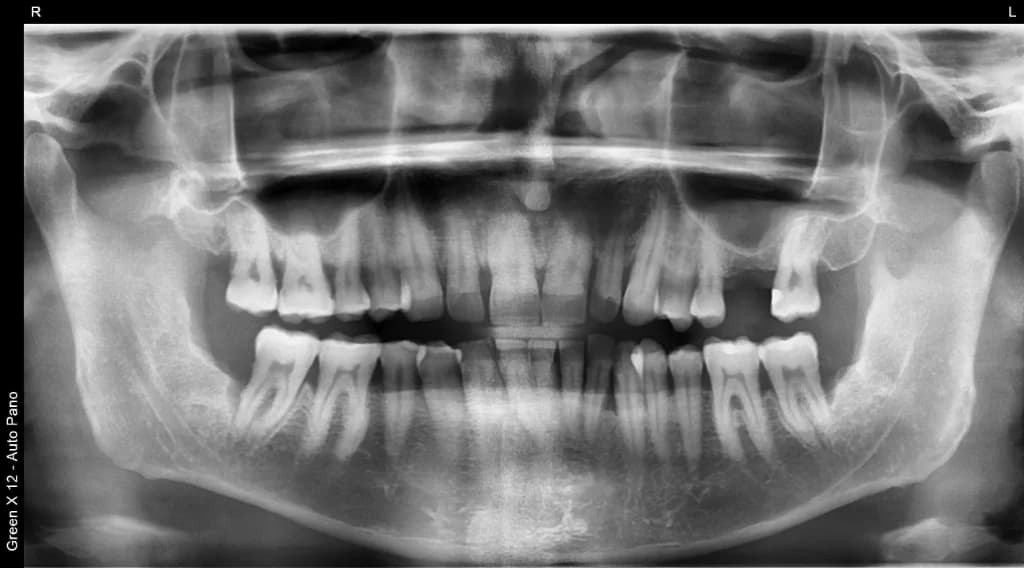

Panoramic X-Rays: The Complete Picture

Panoramic x-rays capture your entire mouth—all teeth, upper and lower jaws, sinuses, and TMJ joints—in a single, wide-angle image. It's like a dental "panorama" that shows relationships between structures.

We use panoramic x-rays for comprehensive exams, orthodontic planning, wisdom teeth evaluation, and screening for jaw abnormalities. The process takes about 10 seconds—you simply stand still while the machine rotates around your head.